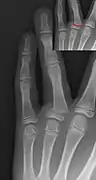

Additional images